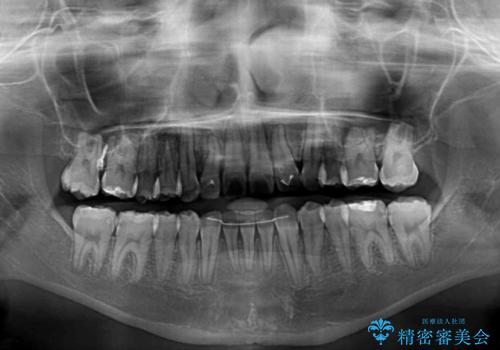

まずは補助装置を用いて八重歯を改善し、インビザラインにて歯列を整えましたが、当初の懸念が的中し、臼歯部の咬合を安定させることができませんでした。

海外留学の予定もあったため、後半は上下ワイヤー装置にて矯正治療を継続し、違和感なく咬合させることとなりました。